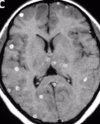

Captación metástasis

En anillo y con edema perilesional